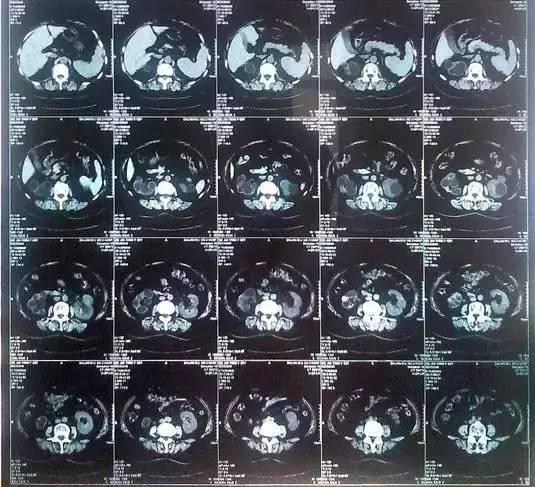

55歲的老何是金華東陽市橫店鎮(zhèn)人,一名普通工人。因為頻繁腰疼去醫(yī)院檢查,結(jié)果CT顯示,他的左腎里竟然密密麻麻布滿了石頭,幾乎把整個腎都塞滿了,手術(shù)從左腎取出了420顆結(jié)石!

醫(yī)生看了CT的結(jié)果顯示,非常嚴(yán)肅的告訴他,他的左腎已經(jīng)被結(jié)石占滿,必須馬上手術(shù)治療。這次手術(shù)讓主刀醫(yī)生觸目驚心,他們居然從老何的左腎取出了420顆結(jié)石。這是他們手術(shù)生涯上從來沒有遇到過的病例。